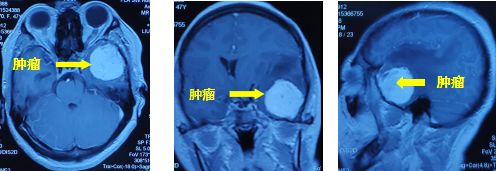

一个月前,47岁的张大姐不幸遇上车祸,在当地医院进行右胫骨上段骨折切开复位内固定术。住院期间,头颅MRI检查提示左颞叶占位。骨折好转出院后,为进一步检查脑袋里面的问题,张阿姨来到重庆主城,在外院行头颅MRI 检查提示"左侧颞部占位,考虑偏恶性肿瘤性病变,脑膜瘤?血管外皮细胞瘤?"

肿瘤周围水肿明显

中线移位

经过充分考虑,患者同意手术!由首都医科大学三博脑科医院专家、我院神经外科主任孙玉明主刀,彭俊副主任医师配合,在全麻下为患者进行左侧额颞入路左颞叶肿瘤切除术。